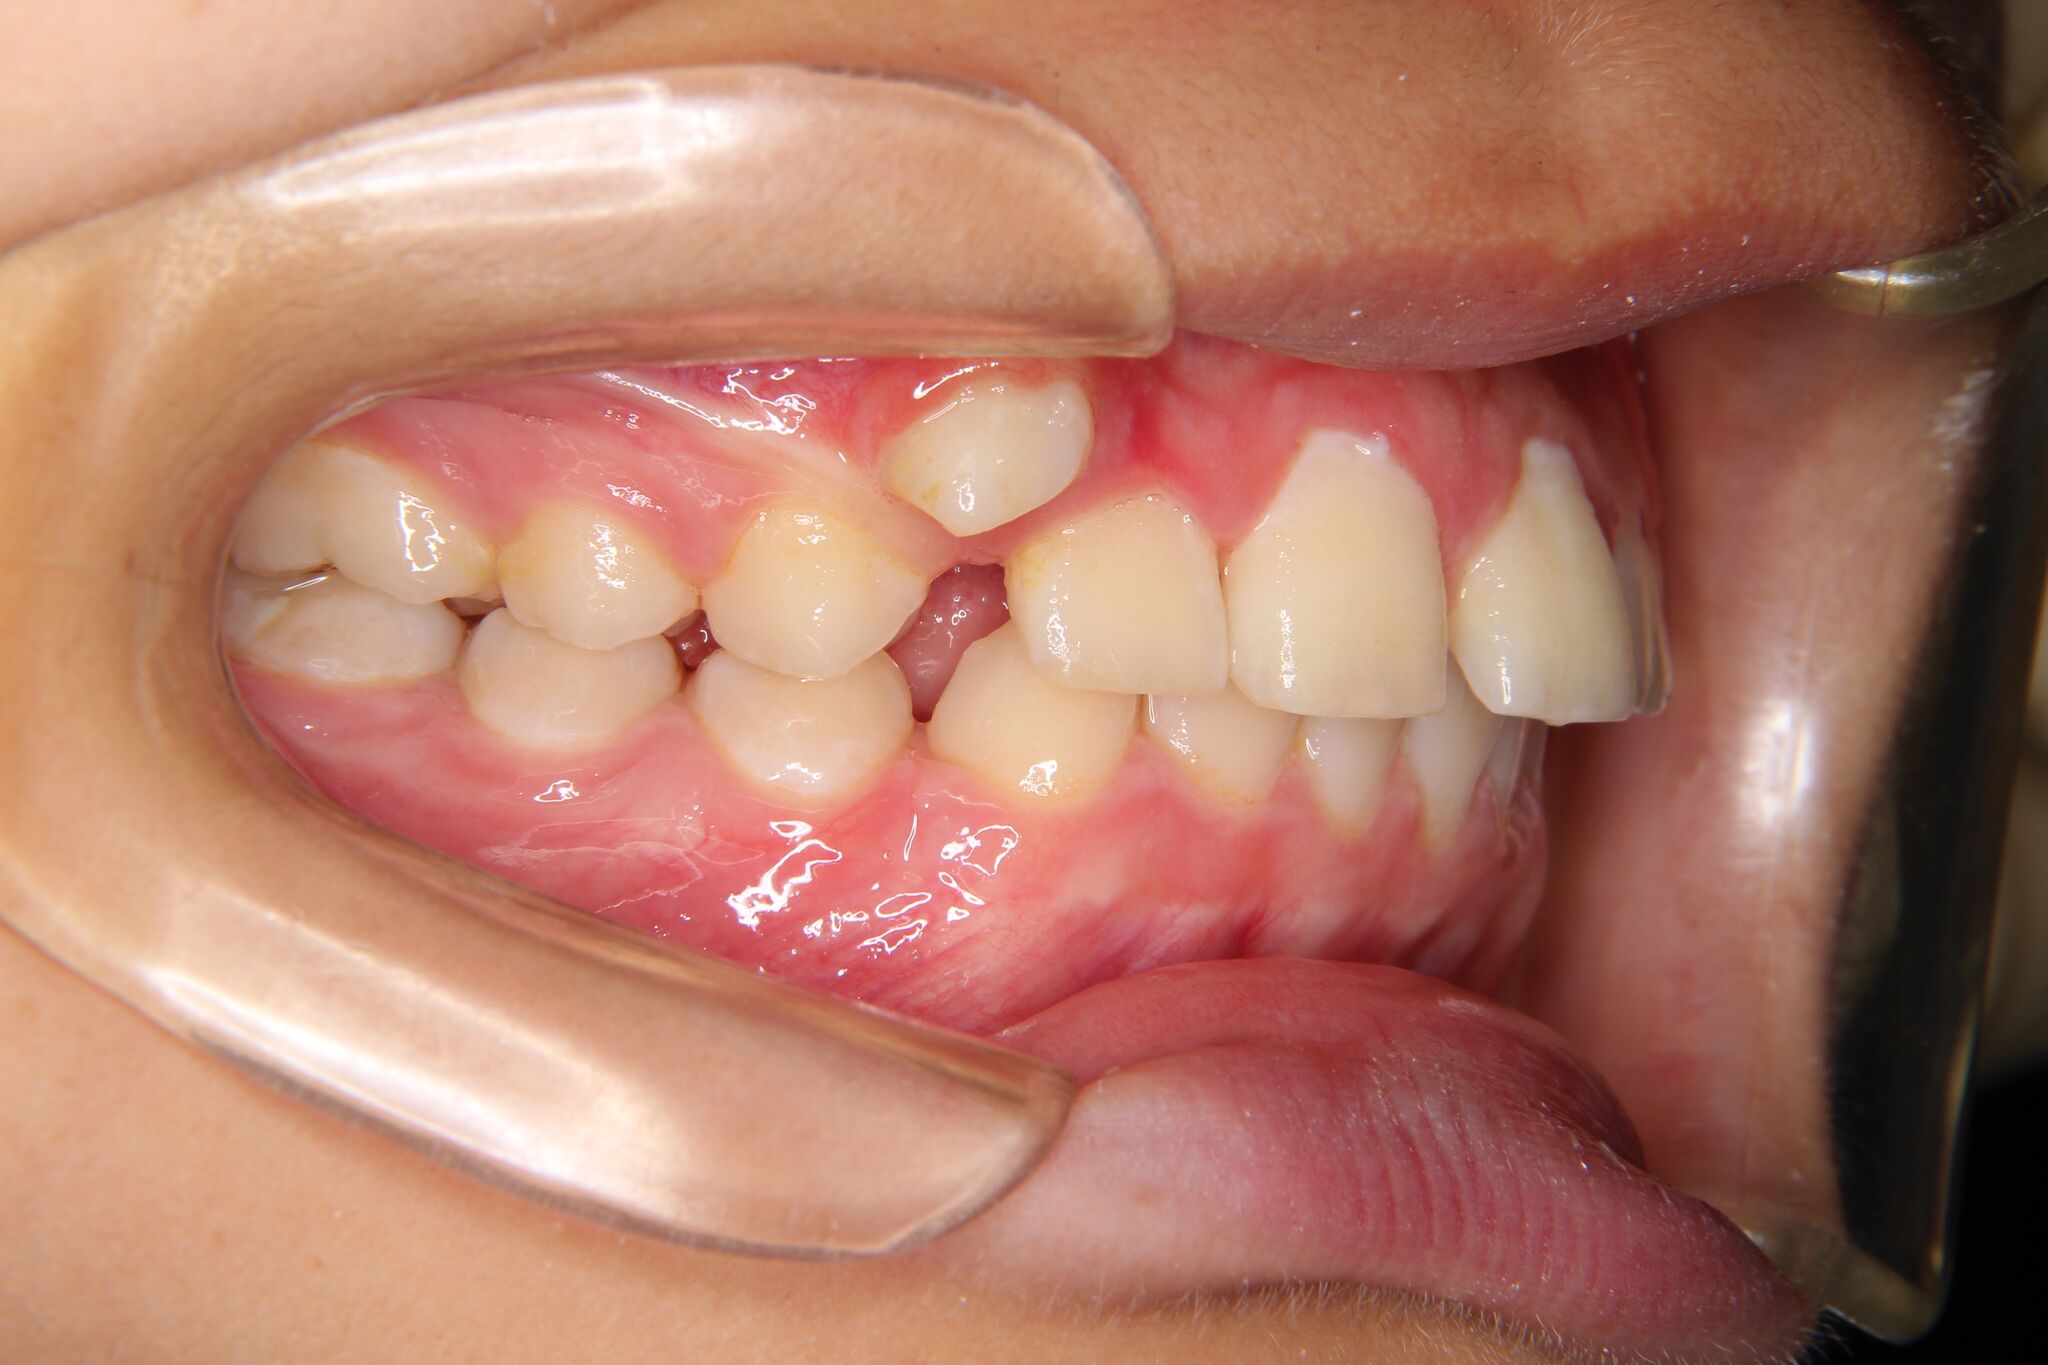

【小学生男子】深い噛み合わせ・上顎の犬歯スペース不足の矯正歯科治療

噛み合わせが深く、上下奥歯の関係のズレがみられました。

バイトプレート(噛み合わせの高さを挙げる装置)とヘッドギア(奥歯を後方に下げる装置)併用しました。

その後、ワイヤーをセットし、犬歯を下ろしてきました。